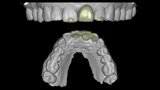

Fig. 20: Temporary crown designed in coDiagnostiX (Dental Wings).